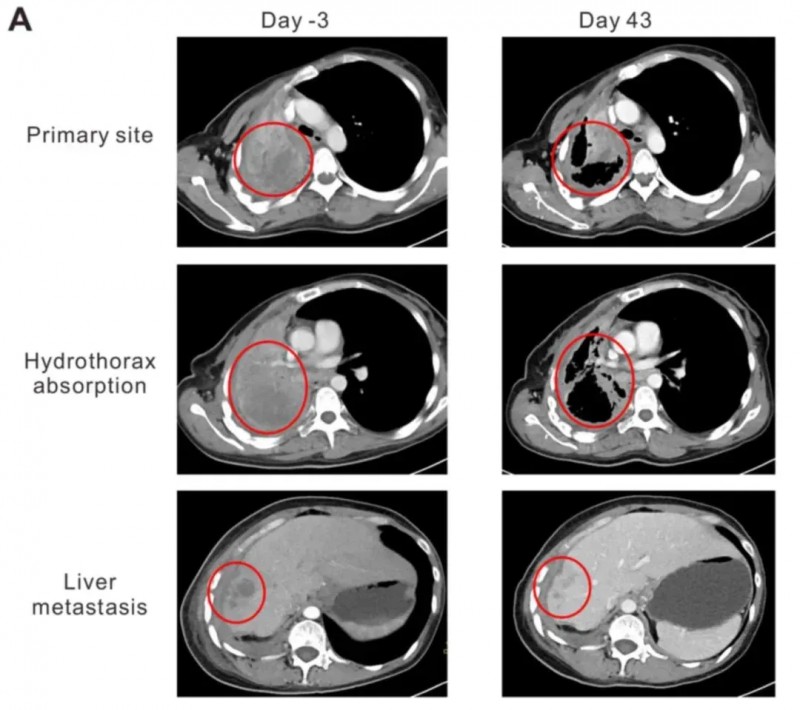

从化疗+靶向治疗失败到部分缓解!NY-ESO-1 TCR-T疗法让晚期肺癌绝境翻盘,43天实现肿瘤消退

NY-ESO-1是癌症免疫治疗中极具潜力的靶点,兼具良好的安全性与有效性,在11.8%-21%的非小细胞肺癌中均有表达。近期,知名期刊《Oncology Letters》报道了一则亮眼案例:通过NY-ESO-1特异性TCR-T细胞疗法治疗晚期非小细胞肺癌,成功使患者肿瘤明显缩小,达到部分缓解(PR)。

该案例患者为44岁女性,确诊为NY-ESO-1阳性晚期肺腺癌(LADC),且携带HLA-A2阳性与EGFR突变。此前她已接受多线治疗但均告失败:先完成6个周期的多西他赛联合卡铂化疗,疾病仍持续进展;后续尝试吉非替尼、厄洛替尼治疗,依旧无法控制病情。2015年9月随访CT显示,其右肺门、纵隔、右胸膜、右肝叶及肝包膜均出现疾病进展(PD),临床已无更合适的治疗方案。转机出现在右肺肿瘤支气管镜活检——标本免疫组化染色呈强NY-ESO-1阳性,这使她成功入组NY-ESO-1 TCR-T细胞治疗临床试验。

治疗效果远超预期:首次TCR-T细胞输注后第43天(2016年1月),CT扫描显示患者肺原发灶与肝转移灶均开始消退,胸水吸收且肺复张。具体数据为:肺原发灶从95×86×54mm缩小至64×44×54mm,肝转移灶从19.8×19.6×20mm缩小至10×10×10mm。依据RECIST 1.1标准评估,患者达到部分缓解(PR)。同时,她的卡氏功能状态评分(KPS)从治疗前的50分提升至90分,咯血、胸痛症状明显缓解,临床症状得到显著改善。